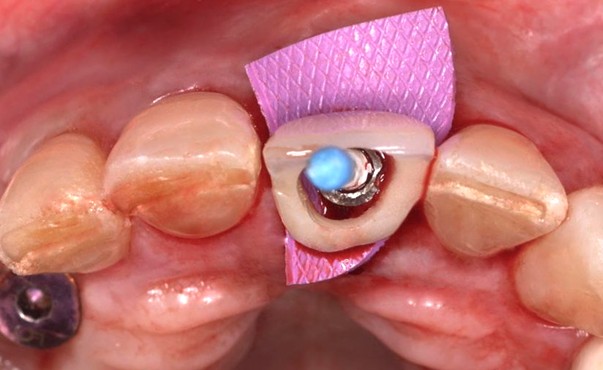

Detección de manipulaciones radiográficas en Endodoncia: la inteligencia artificial en la lucha contra el fraude radiográfico